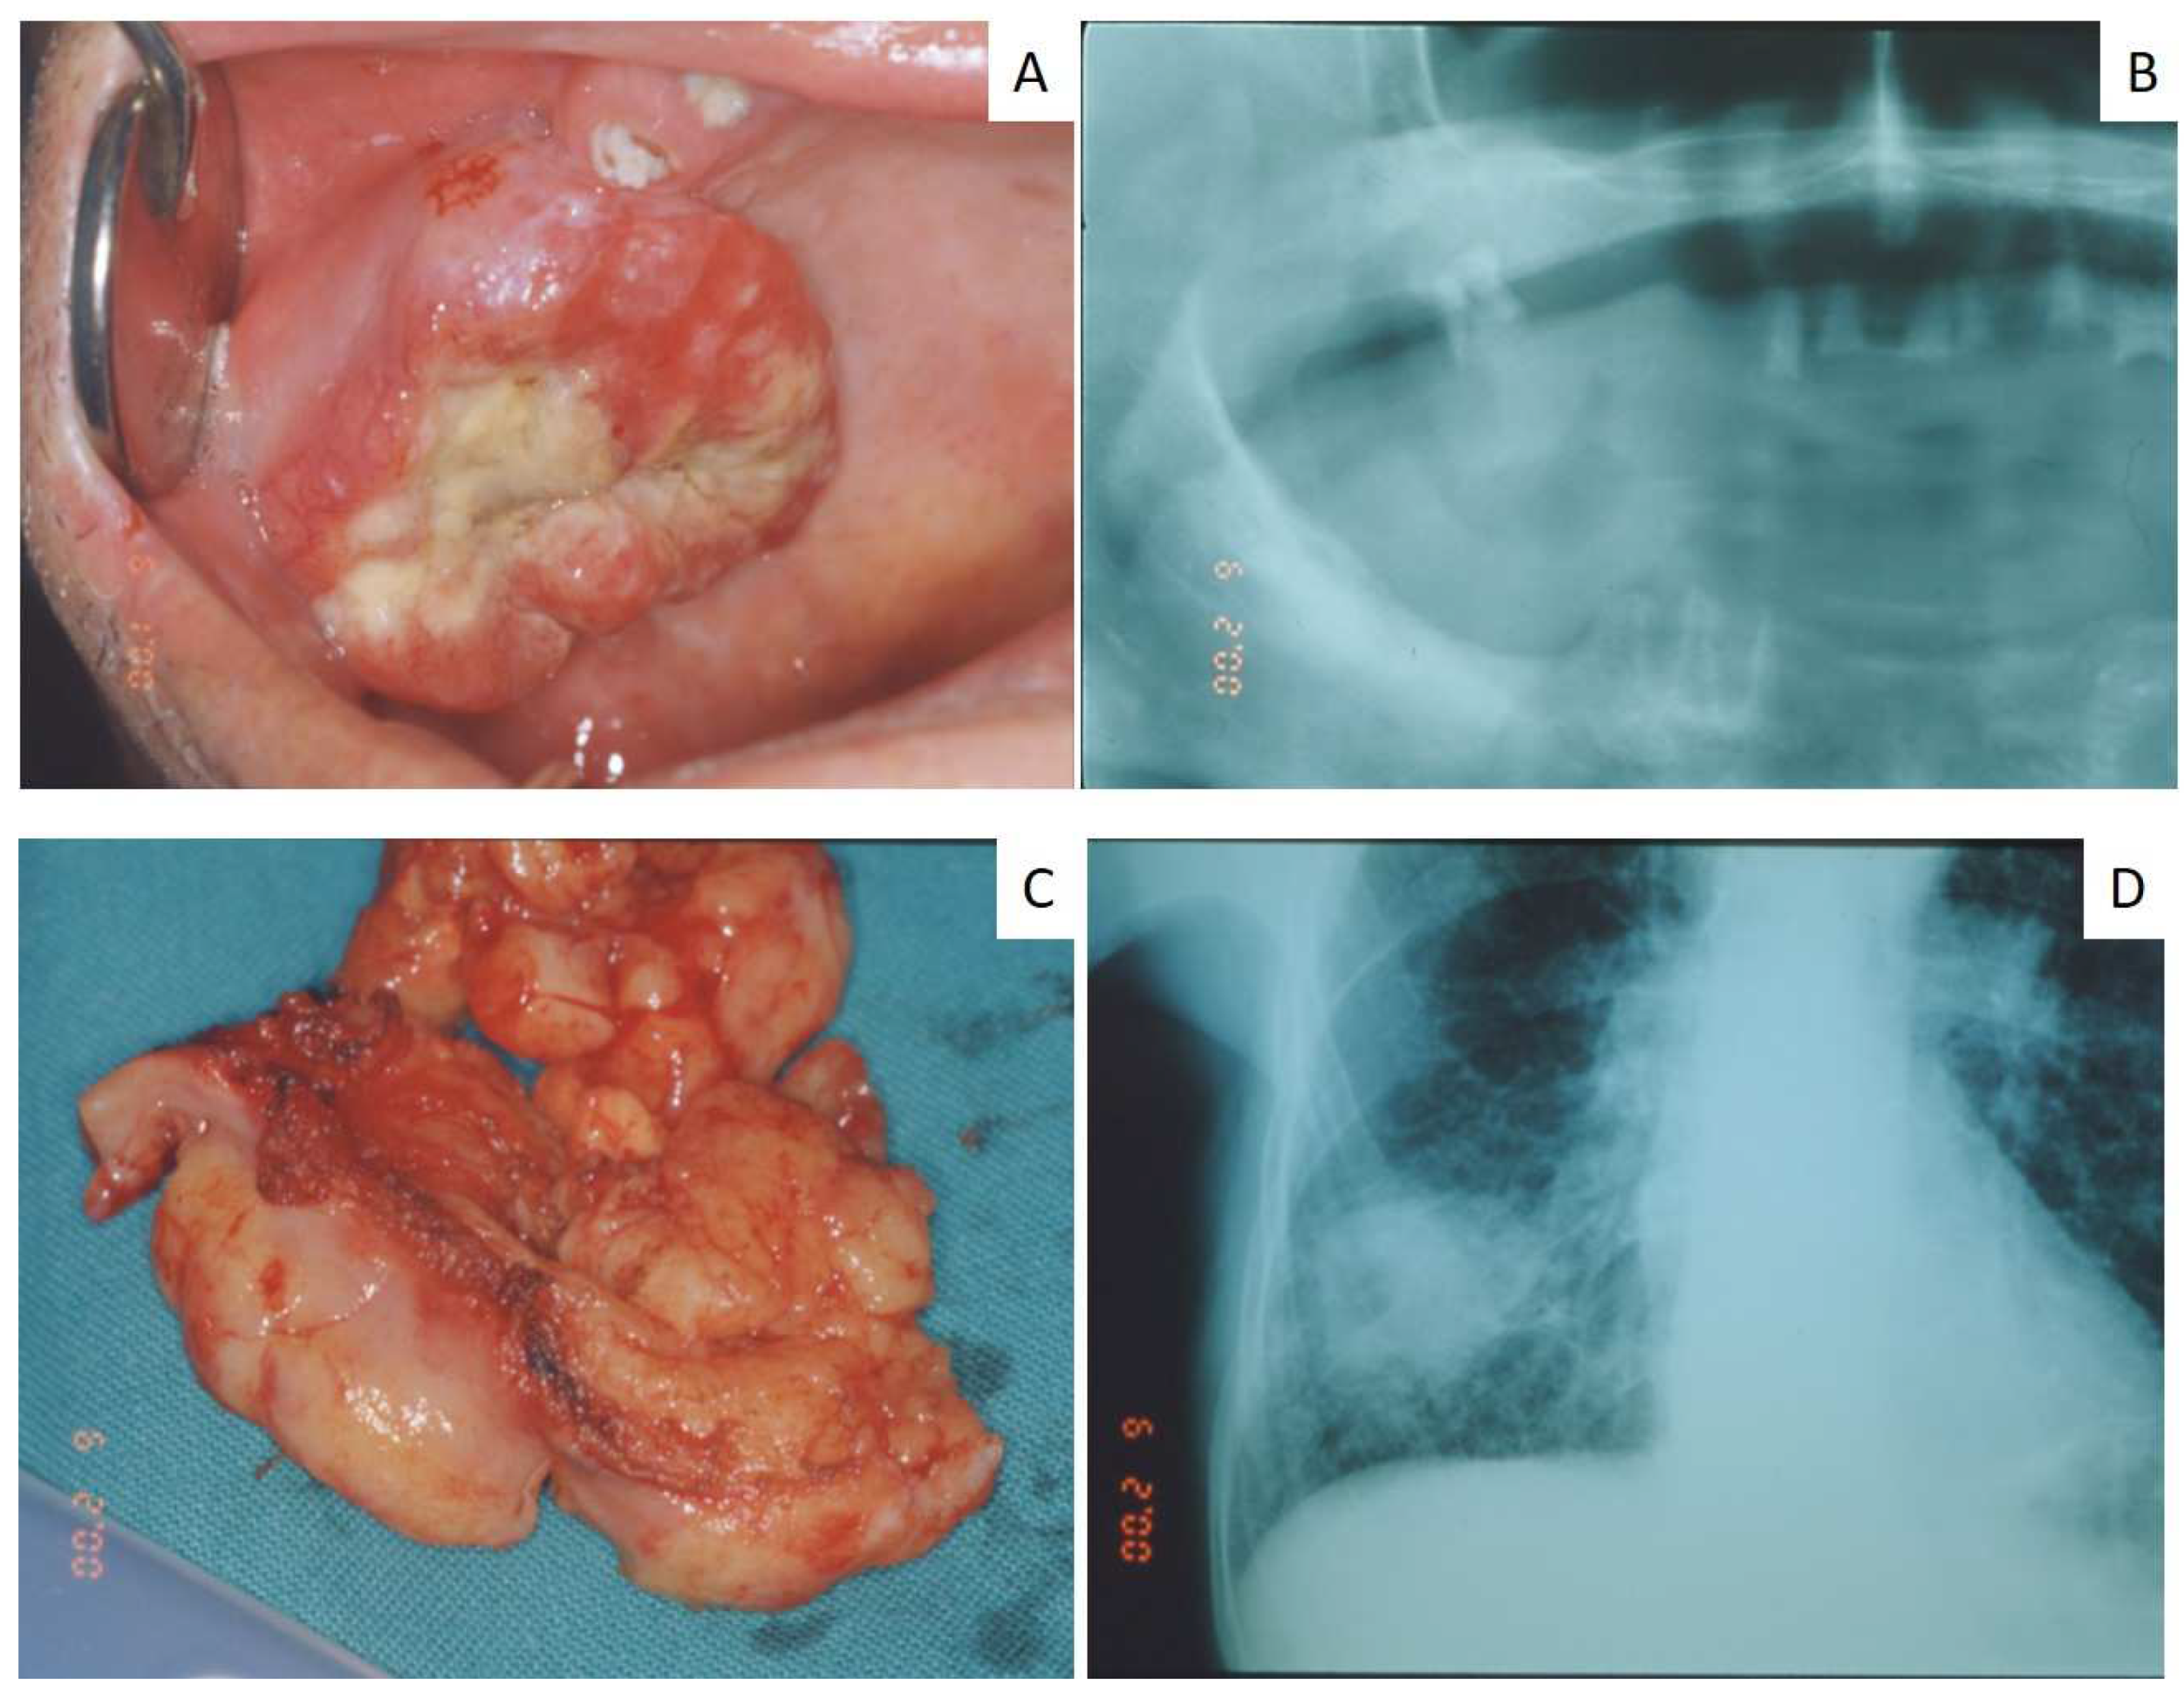

| 14 | 80 | M | Mandible | Squamous carcinoma | Vertebra | No |

| 15 | 67 | M | Maxillary gingiva | Squamous carcinoma | Vertebra | No |

| 16 | 65 | M | Parotid gland | Small cell carcinoma | n.a. | Yes |

| 17 | 70 | F | Maxillary gingiva Around dental implant | Small cell carcinoma | n.a. | Yes |

| 18 | 62 | M | Maxilla gingiva Around dental implant | Adenocarcinoma | n.a. | Yes |